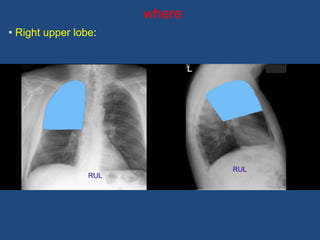

where

• Right upper lobe: